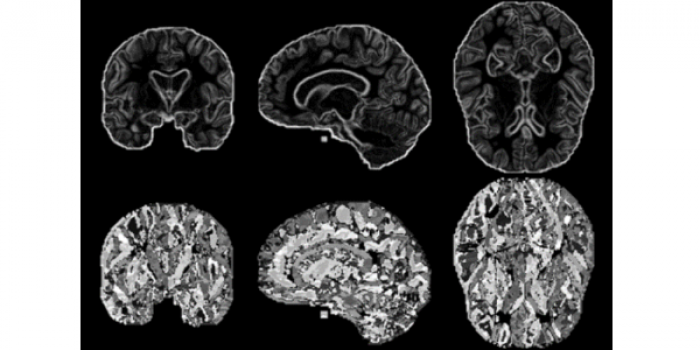

Alzheimer’s Disease (AD) is a neurodegenerative pathology characterized by progressive atrophy of brain and impairment of memory and cognitive functions. Physicians frequently use structural brain imaging to identify abnormal patterns in brain structure that may indicate probable AD. Thus, shape information is central for brain imaging analysis and AD diagnosis. This paper examines how three variants of Pyramid Histograms Of visual Words (PHOW) descriptions, a data-driven approach, handle the complex task of AD classification. 87 pathological cases and 87 controls from OASIS dataset were used to study the impact of shape and surface information. Best performance was 89.3%, a current mark for AD classification, and an increase (27.1%) in contrast to a naive approach. Additionally, controls were better classified than demented subjects (94.5% and 84.0%, respectively), while young, early-onset AD subjects, and elderly controls were the most difficult. Finally, dictionary word analysis revealed discriminative surface features. Also, local patterns induced by global word distribution appear to be more significant for classification than word location.